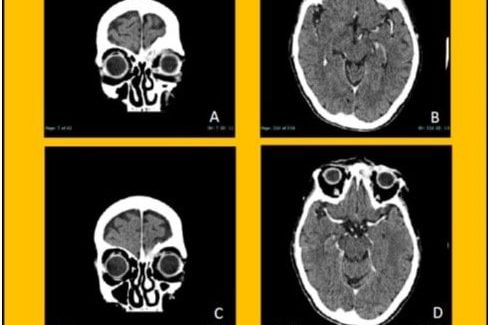

Sindrome di eagle – algie dell’articolazione temporo mandibolare

Paziente di 65 aa. Sofferente da 20 anni.

Inviata colleghi terapia antalgica per algie non specifiche all’ ATM che si accompagnavano a cefalea, otalgia, dolori regione faringea che comparivano ruotando il collo.